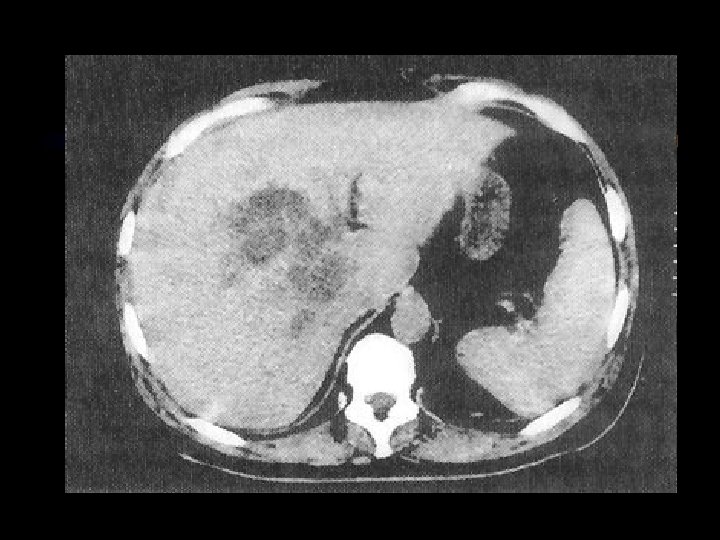

Pankreas Akut pankreatitis Karın ağrısı, bulantı-kusma, şok Nedenler Safra kesesi-yolları taşları Alkol Virüsler Hiperlipidemi, İatrojenik Tanı Serum amilazı yükselir Abd. CT ve US komplikasyonlar pseudokist, flegmon abse